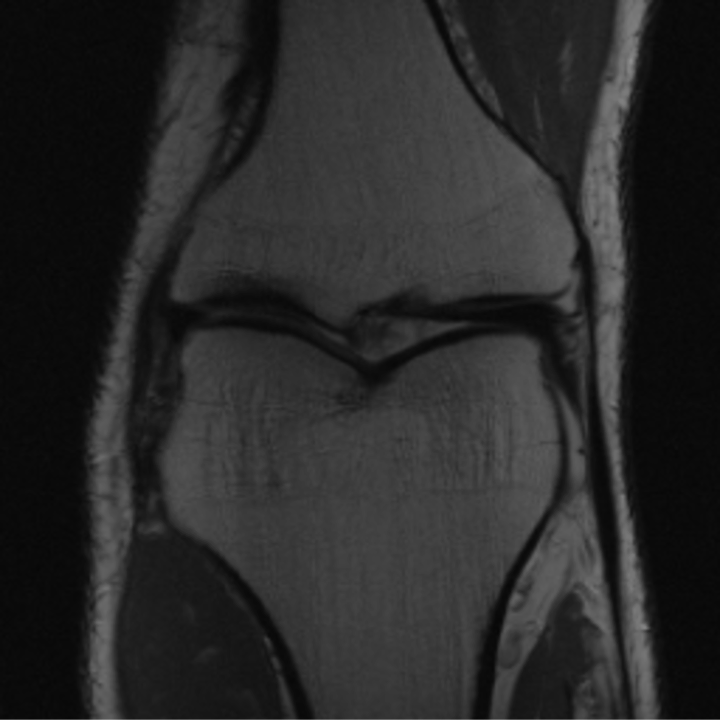

5.3 Out-of-Domain Generalisation

One way to test the generalization capability of the trained X-Diffusion is to test it on a completely different domain from an MRI dataset not seen during training. We report the single-slice results on NYU fastMRI [37, 82], a knee MRI dataset, using the X-Diffusion trained on the BRATS brain MRIs. The results are shown in Figure 9 and Table 2. It shows how successfully X-Diffusion is able to generate knee MRIs from a single image, despite not seeing knees at all in training. To qualitatively assess how realistic our generated 3D volumes were (produced from a single slice), we gave 20 generated examples alongside their real MRI counterparts to an expert orthopaedic surgeon. He was then asked to identify the real example from a given pair. The surgeon identified with certainty only 10 real knee MRIs out of 17, while could not decide on the remaining 3 of the 20 MRI pairs. This further validates the generated out-of-domain MRIs.